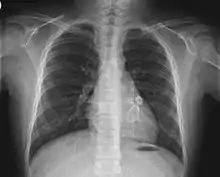

Cardiac

Heart complications are the most important aspect of Kawasaki disease, which is the leading cause of heart disease acquired in childhood in the United States and Japan.[31] In developed nations, it appears to have replaced acute rheumatic fever as the most common cause of acquired heart disease in children.[15] Coronary artery aneurysms occur as a sequela of the vasculitis in 20–25% of untreated children.[52] It is first detected at a mean of 10 days of illness and the peak frequency of coronary artery dilation or aneurysms occurs within four weeks of onset.[48] Aneurysms are classified into small (internal diameter of vessel wall <5 mm), medium (diameter ranging from 5–8 mm), and giant (diameter > 8 mm).[31] Saccular and fusiform aneurysms usually develop between 18 and 25 days after the onset of illness.[15]

Even when treated with high-dose IVIG regimens within the first 10 days of illness, 5% of children with Kawasaki disease develop at the least transient coronary artery dilation and 1% develop giant aneurysms.[53][54][55] Death can occur either due to myocardial infarction secondary to blood clot formation in a coronary artery aneurysm or to rupture of a large coronary artery aneurysm. Death is most common two to 12 weeks after the onset of illness.[15]

- Electrocardiogram may show evidence of ventricular dysfunction or, occasionally, arrhythmia due to myocarditis.

- Echocardiogram may show subtle coronary artery changes or, later, true aneurysms.

- Angiography was historically used to detect coronary artery aneurysms, and remains the gold standard for their detection, but is rarely used today unless coronary artery aneurysms have already been detected by echocardiography.